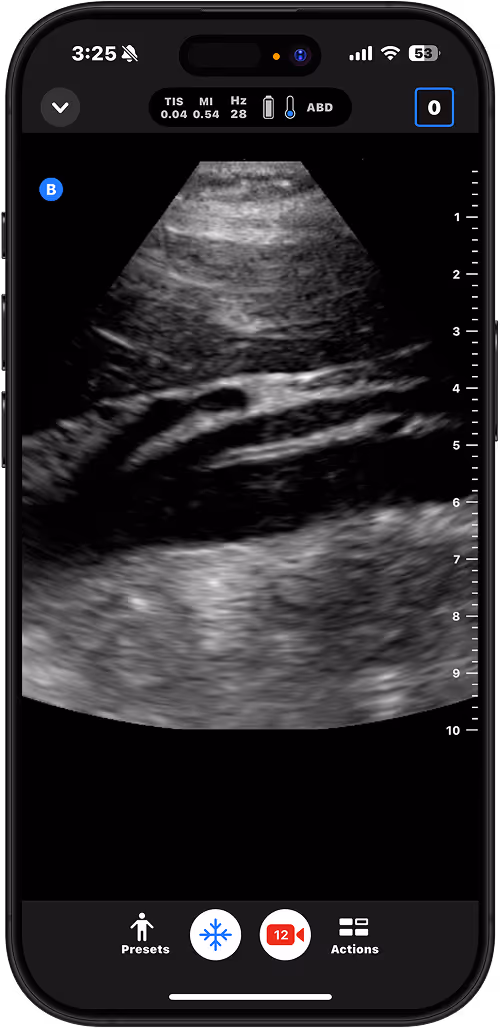

Perform bedside assessment for pneumonia, CHF, asthma exacerbation, or pneumothorax.

Calculate bladder volume to support urinary retention management.